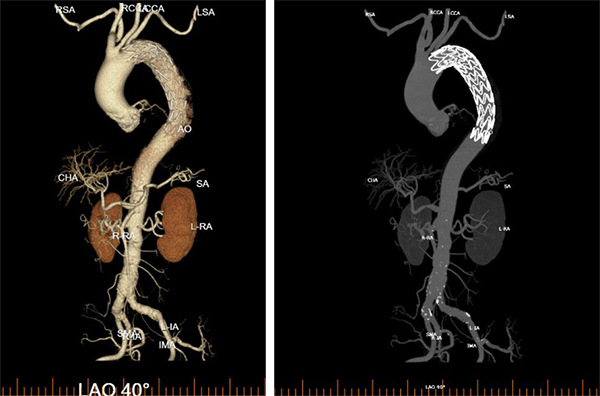

术中,周围血管科团队凭借丰富的临床经验和精湛的手术技艺,精准定位主动脉破口,成功植入覆膜支架,完整修复了撕裂的血管内膜,隔绝了假腔血流。术后造影显示支架位置良好,主动脉破口完全封闭,手术取得圆满成功。